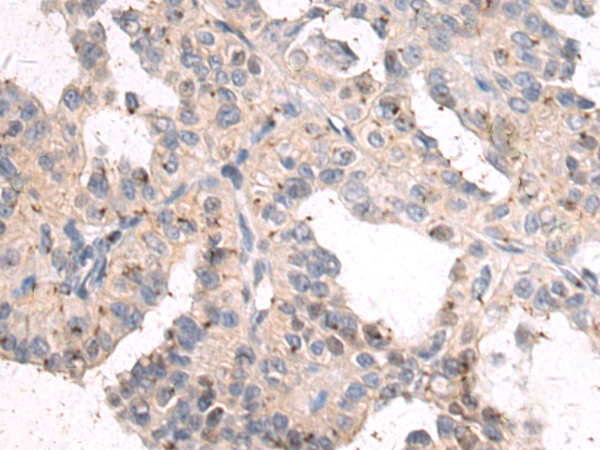

分类: 科研抗体货号: P10604别名: MCS; MOS; HMCS应用: IHC反应种属: Human